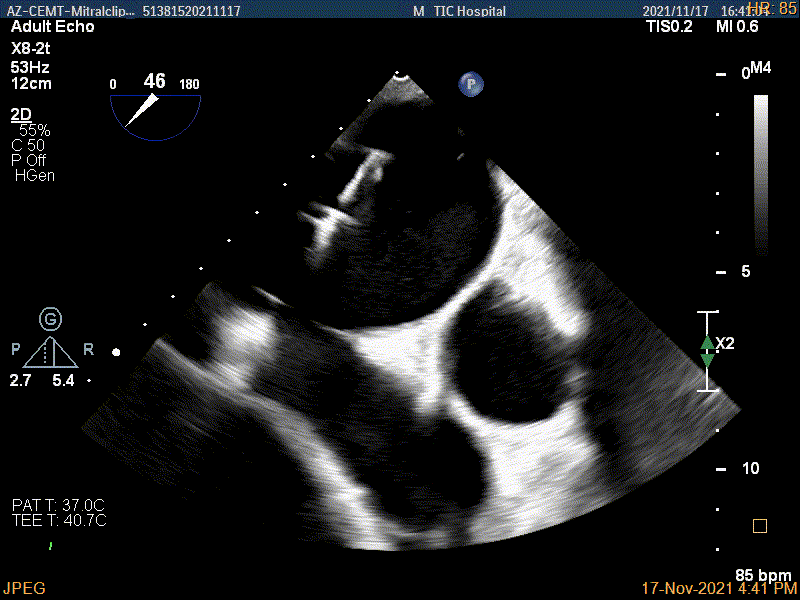

确定房间隔穿刺点

2D视图观察夹子经过大鞘进入左房内